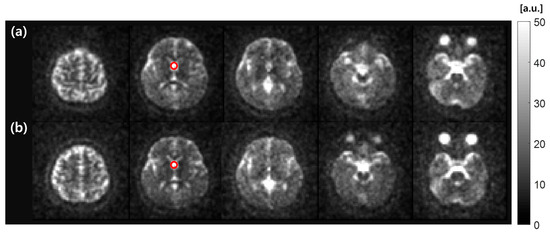

In the assessment of the RF coil performance for 1H MRI, SNR maps using 1H STBC and 1H/23Na DMBC RF coils are presented in Figure 7. The mean SNR value in ROI was 83.3 for 1H STBC RF coil and 77.9 for 1H/23Na DMBC RF coil, indicating a 6.5% SNR reduction with the DMBC RF coil.

Figure 7. SNR maps of in vivo human head 1H MR images acquired with (a) 1H STBC RF coil and (b) 1H/23Na DMBC RF coil. Red circles indicate the ROI for the SNR measurement.

Similarly, for the 23Na MRI test, the SNR maps of a human head are presented in Figure 8. The maps compare MR images acquired using 23Na STBC and 1H/23Na DMBC RF coil. The mean SNR values within the cerebrospinal fluid (CSF) ROI were 41.9 vs. 39.8 for STBC 23Na and 1H/23Na DMBC RF coil, respectively. This minor difference represents a nominal 5.4% reduction in SNR with the 1H/23Na DMBC RF coil, which is nearly comparable to the performance of the 23Na STBC RF coil.

Figure 8. SNR maps of 23Na MR images of an in vivo human head using (a) 23Na STBC RF coil and (b) 1H/23Na DMBC RF coil. Red circles overlaid on CSF designate the area for SNR measurement.